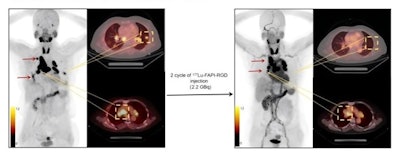

The researchers first performed gallium-68 (Ga-68) FAPI-RGD-PET/CT scans on the nine patients to confirm tumor uptake. All patients received an injection of Lu-177 DOTA-FAPI-RGD in a dosage of 2.2 GBq (60.2 mCi). They then performed safety tests every two weeks after the first treatment for six to eight weeks, which was defined as a one treatment cycle. After one treatment cycle, patients underwent a second  Ga-68 FAPI-RGD PET/CT scan to evaluate the preliminary efficacy of the treatment.A 56-year-old woman with disease progression after surgery received Lu-177 FAPI-RGD at 2.2 GBq/cycle. Baseline Ga-68 FAPI-RGD PET/CT revealed intense Lu-177 FAPI-RGD uptake in most metastatic lesions including lymph node and lung modules (left, arrows and square box). After two treatment cycles, a restaging Ga-68 FAPI-RGD-PET/CT scan revealed a significant reduction in tumor size in most of the metastatic lesions. Furthermore, most of the lesions in the lungs have disappeared (right, arrows and square box).A 56-year-old woman with disease progression after surgery received Lu-177 FAPI-RGD at 2.2 GBq/cycle. Baseline Ga-68 FAPI-RGD PET/CT revealed intense Lu-177 FAPI-RGD uptake in most metastatic lesions including lymph node and lung modules (left, arrows and square box). After two treatment cycles, a restaging Ga-68 FAPI-RGD-PET/CT scan revealed a significant reduction in tumor size in most of the metastatic lesions. Furthermore, most of the lesions in the lungs have disappeared (right, arrows and square box).Jialing Xiang and SNMMI

According to the results, Lu-177 DOTA-FAPI-RGD was well tolerated by all patients, with no noticeable side effects reported. Significant uptake and long tumor retention of Lu-177 FAPI-RGD resulted in high absorbed tumor doses, such as 4.3 Gy/GBq in lung metastases and 4 Gy/GBq in peri-metastases, Xiang reported.